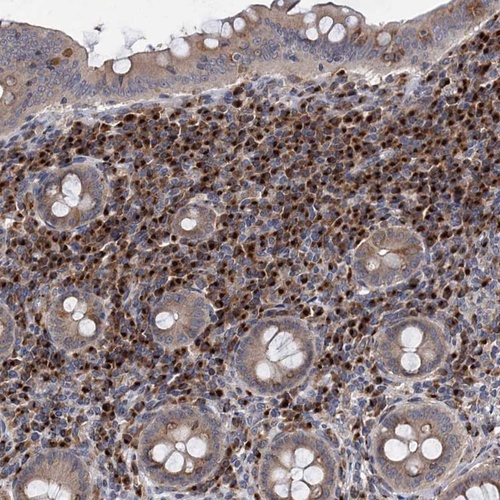

Immunohistochemical staining of human appendix shows cytoplasmic positivity in lymphoid tissue.